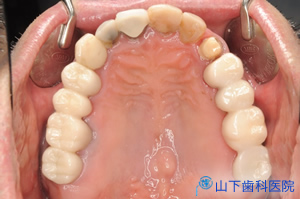

| 上顎の残っている歯すべてに金属製の内冠または沈下を抑える根面板を被せています。 | ![]() |

| 外冠が付いている「入れ歯」は味覚を落とさないよう、口蓋を中抜きした金属床です。 | ![]() |

| 内冠部分に外冠ブリッジをはめ込み、インプラント部分に上部構造体をネジ止め固定した状態です。口蓋は完全に開放され、もはや入れ歯ではなくなりました。 | ![]() |

| 前方から見たところです。 | ![]() |